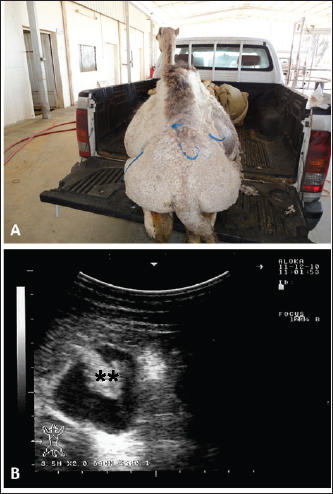

Full details including presenting complaints, symptoms, diagnosis, treatment, and outcome of the 25 dromedary camels with depraved appetites are listed in Table 1. The dromedary camels with depraved appetites had different presentations, but all of the examined animals had a history of eating foreign or inanimate objects. Pica was evident in some cases upon initial clinical examination (Fig. 1). Twelve of the camels (48%) were admitted with a history of loss of body weight and 8 (32%) with partial or complete loss of defection. Seven out of the nine (77.8%) lactating camels in this study suffered from decreased milk production. An example of such a case is shown in Figure 2. In animals undergoing laparotomy, the foreign bodies were surgically removed as shown in Figure 3. Bouts of repeated vomiting were also found in 5 (20%) of the camels. In animals that underwent rumenotomy, the foreign bodies were removed as in Figure 4. Eating feces (coprophagia) was also found in six camels as shown in Figure 5. Sixteen (64%) of the camels were recovered while the remaining 9 (36%) did not survive.

Sonographic and postmortem findings are summarized in Table 2. In cases of camels presented with a history of pica and with decreased or total absence of feces, the obstructing foreign body was imaged in 10 of the 25 camels (40%) occluding completely or partially the intestines that may be confirmed at abdominal surgery (Figs. 2, 3, and 6). Foreign bodies within the rumen could not be visualized with ultrasound owing to the gas content. In cases where the rumen is impacted by sand, small pin-points revealing acoustic enhancement were imaged in 5 (20%) of the camels. An example of these cases is shown in Figure 7. Foreign bodies were removed from the rumen or intestines at exploratory rumenotomy and laparotomy, which included plastics, cloths, sand, mud, robes, wool balls, glasses, or even metallic objects that were blunt or sharp (Figs. 8 and 9).

Fig. 2. Ultrasonographic findings in an adult female camel with a history of pica. The animal was admitted with a 7-day history of decreased fecal output and abdominal distension (A). Image (B) shows an obstructing foreign body occluding the small intestines partially (stars) using a 3.5 MHz sector transducer.